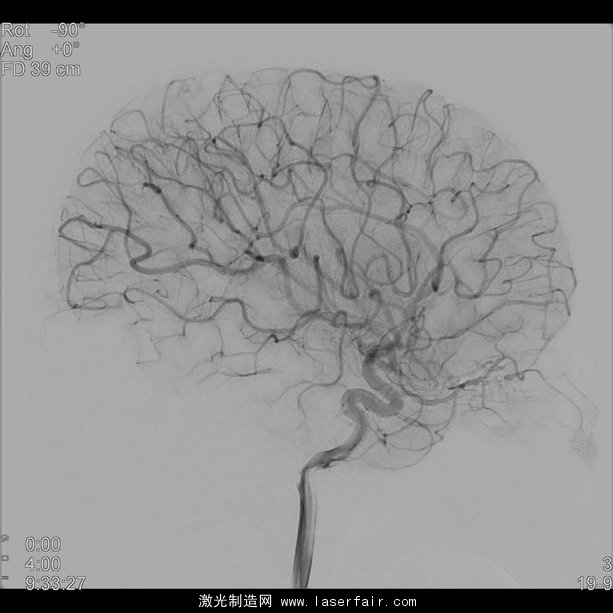

神經(jīng)放射學是放射學的分支之一,包含了大腦、頭頸和脊椎的診斷和微創(chuàng)治療。這些療法需要插入導管,必須在實時圖像引導的幫助下,通過一根非常狹窄(血管不到2mm寬)和彎曲的脈管導航至治療區(qū)域。新設(shè)備(如支架和偏流器)為缺血性中風或大塊頸動脈瘤提供新療法,但其日益縮小的設(shè)計使設(shè)備越來越難使用 X 射線成像進行查看。這會對放置和治療評估造成更多困難。

為應對這些困難,飛利浦的 NeuroSuite 包含一個雙面介入式 X 射線系統(tǒng),并獨家整合了兩款新探測器:飛利浦前額 FD20探測器提供實時的2D 和3D 影像以實現(xiàn)實時導航和即時療法反饋;小型側(cè)面 FD15探測器可放置于遠離雙肩和非常靠近頭部的部位。這樣的更短距離和獨特的探測器結(jié)合,能以更少的 X 射線劑量提供清晰的全腦影像,以及對神經(jīng)與脊椎介入進行了優(yōu)化的3D 影像。

卡羅林斯卡大學醫(yī)院神經(jīng)放射科副主任醫(yī)師、神經(jīng)造影和立體定向主管 Michael Soderman 醫(yī)師說:“血管造影術(shù)系統(tǒng)在介入式神經(jīng)放射科的表現(xiàn)對患者的安全極為重要。飛利浦的最新創(chuàng)新是在額狀面有著20英寸新探測器的 NeuroSuite,能提供極好的3D 影像和足夠大的脊椎影像。側(cè)面則有15英寸的新探測器能提供完整的大腦血管影像,可減少碰撞危險并促進投影自由。”

NeuroSuite 的中心是將放射劑量減少了73%且不犧牲影像品質(zhì)[2],[3]的飛利浦 AlluraClarity,以及在血管背景和血管組織直至穿支血管中可視化顱內(nèi)設(shè)備[1]的VasoCT。